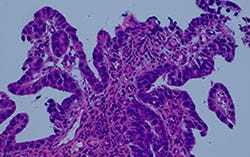

オリンパスの取り組みにより、ハロゲンランプと同等以上の演色性と輝度を提供するTrue Color LEDが生まれました。このLEDランプを備えたBX53顕微鏡は、明視野観察やその他の観察方法に有用です。輝度レベルは、同時観察のためのマルチディスカッションで使用するのに十分な強度であり、信頼できる標本観察に必要とする色再現性を提供します。

図6:26名用マルチヘッドシステム(左)と観察画像(右)